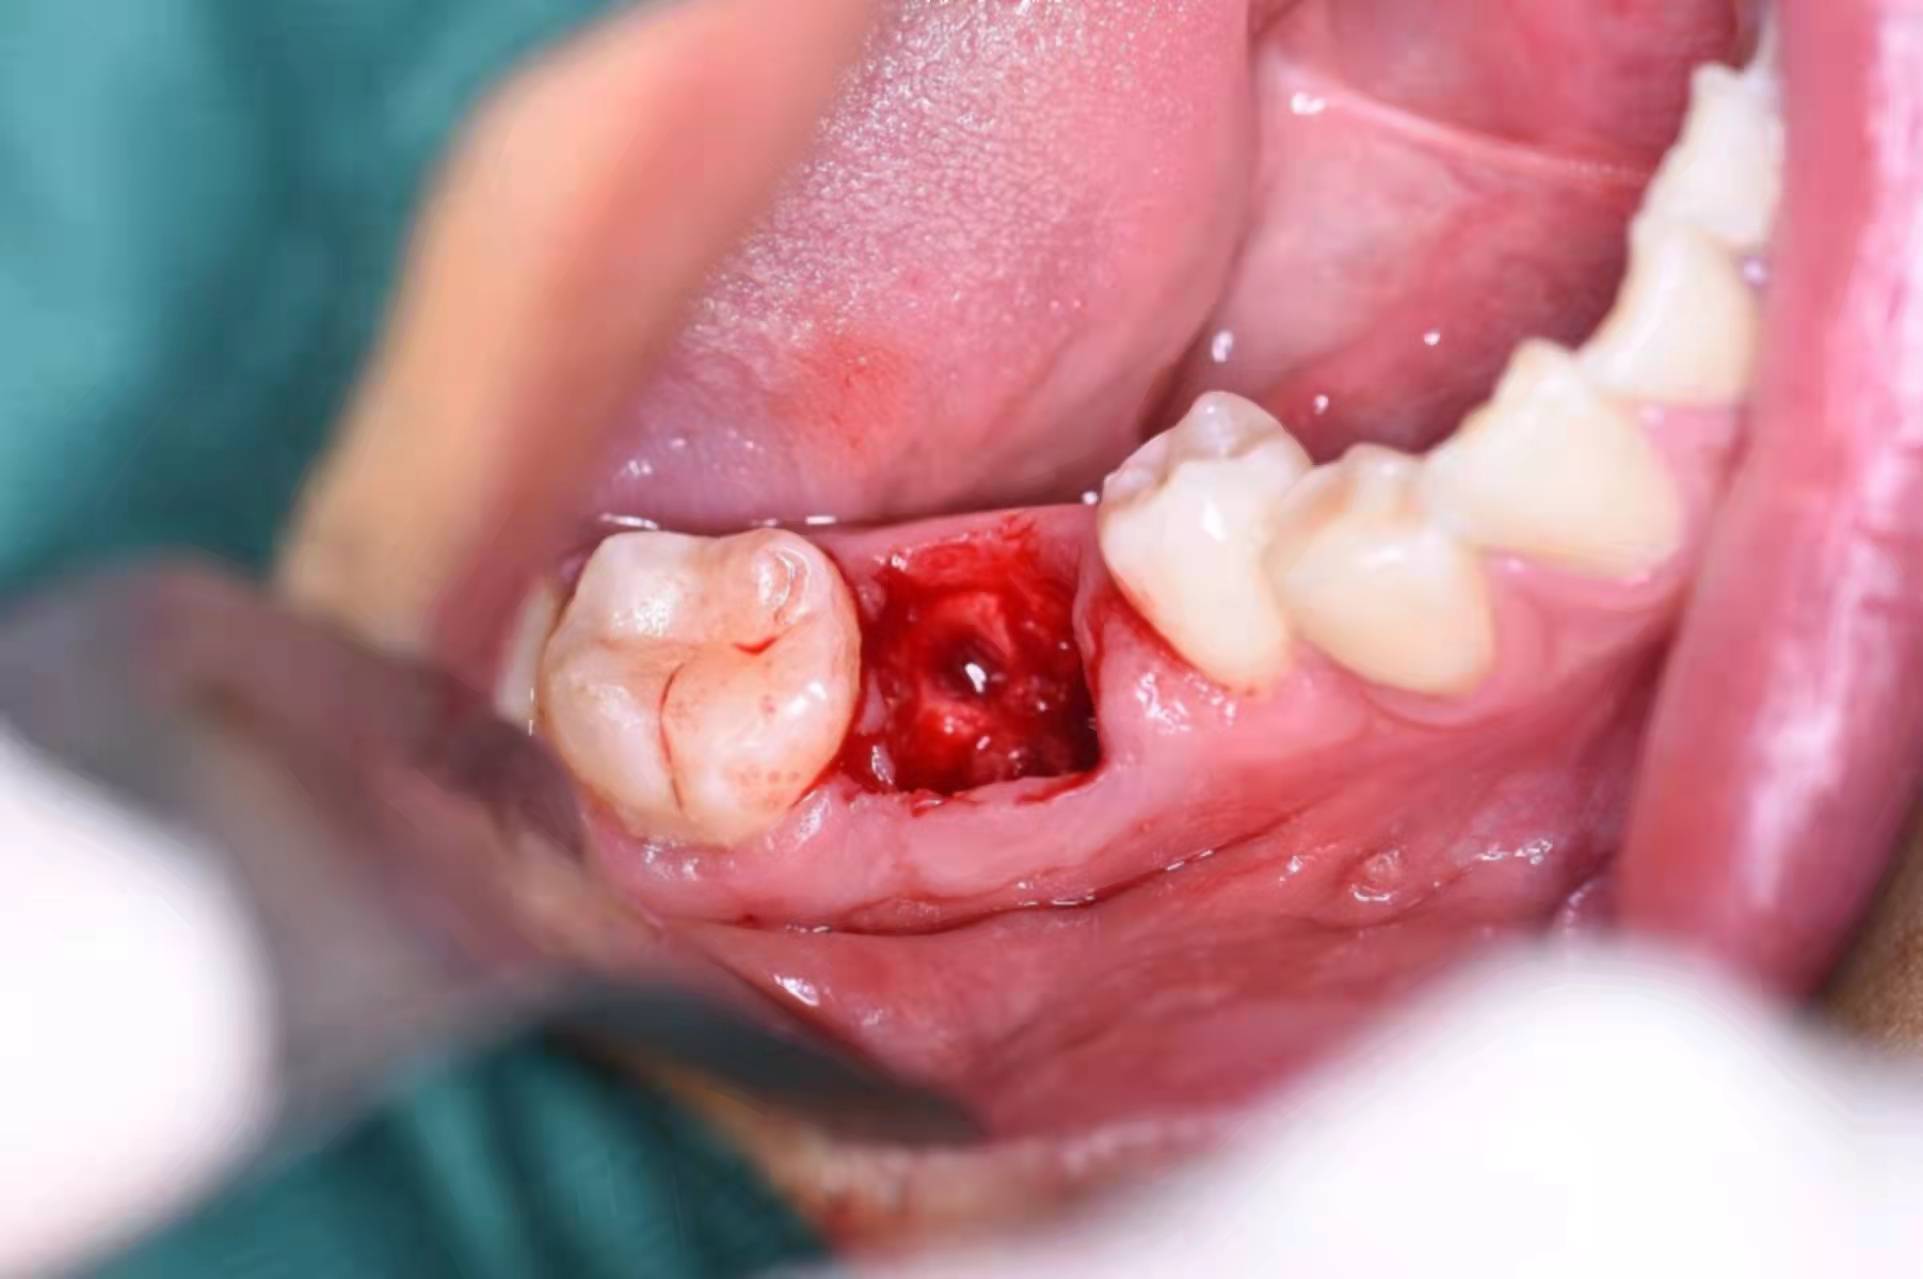

拔下來的殘根,全部拿出:

備洞,準備植入種植體